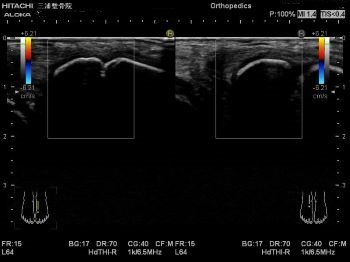

エコーではこのように写ります。

患側では大きく腫れて

正常な靭帯線維が見えないため

二分靭帯が断裂しています。